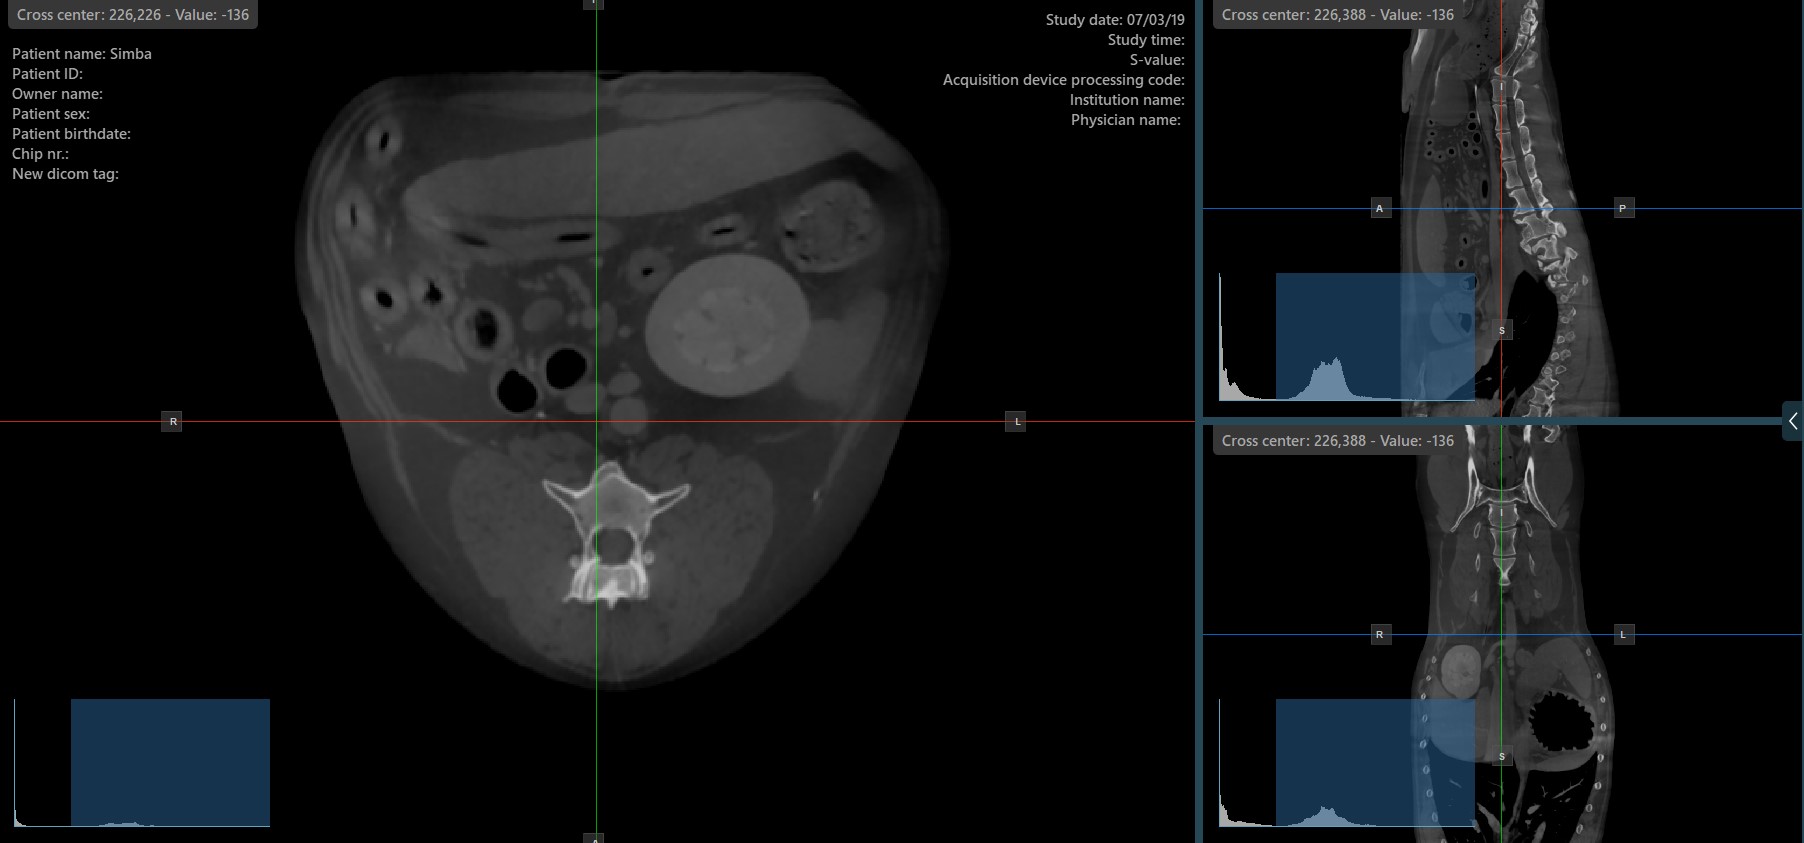

Die Slicer in der MPR-Ansicht zeigen die Schnittpunkte und die Orientierung der drei Bild-Ebenen, die in den aktiven Ansichtsbereichen angezeigt werden. Benutzer können die Slicer ändern und die Querschnittsposition der Schichten basierend auf den 3D-volumetrischen Daten anpassen.

Jeder Slicer ist durch seine spezifische Farbe gekennzeichnet, die die jeweilige Bildebene darstellt:

Der blaue Slicer markiert die axiale Ebene des Objekts (senkrecht zum Boden).

Der rote Slicer markiert die koronale Ebene (parallel zum Boden).

Der grüne Slicer markiert die sagittale Ebene (senkrecht zum Körper).